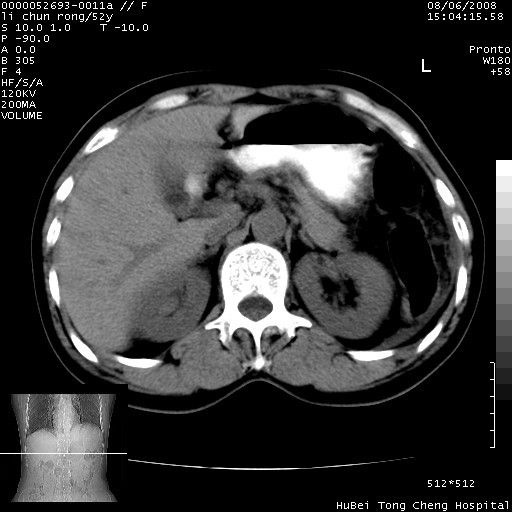

以下是引用云翔在2008-8-7 6:20:00的发言:[br]胰尾部囊性病变,考虑假囊肿,结合实验室检查疾病史

以下是引用zjzjr在2008-8-7 8:38:00的发言:[br]支持胰腺炎伴假囊肿形成,左肾小囊肿.少量腹水.

以下是引用随光逐影在2008-8-7 9:12:00的发言:[br]1)考虑胰腺炎伴假性囊肿形成可能性大;胰腺囊腺瘤待排。2)左肾小囊肿。3)少量腹水。